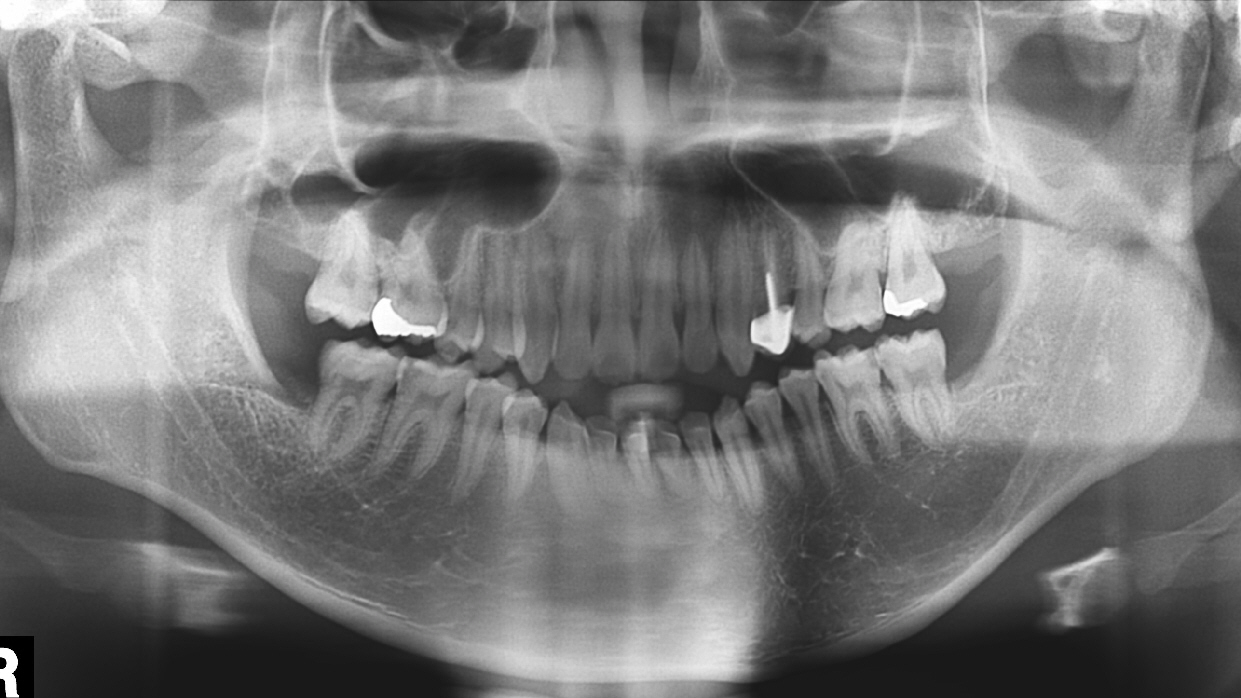

안녕하세요 11361글 작성자입니다. 조언해주신것과 제 생각이 일치하여 재교정 1월에 들어갈 예정인데 질문 있어요. 오른쪽 어금니는 교합이 완전히 어긋나서 안하면 안되겠더라고요. scissor biting 이라고 하네요. ...